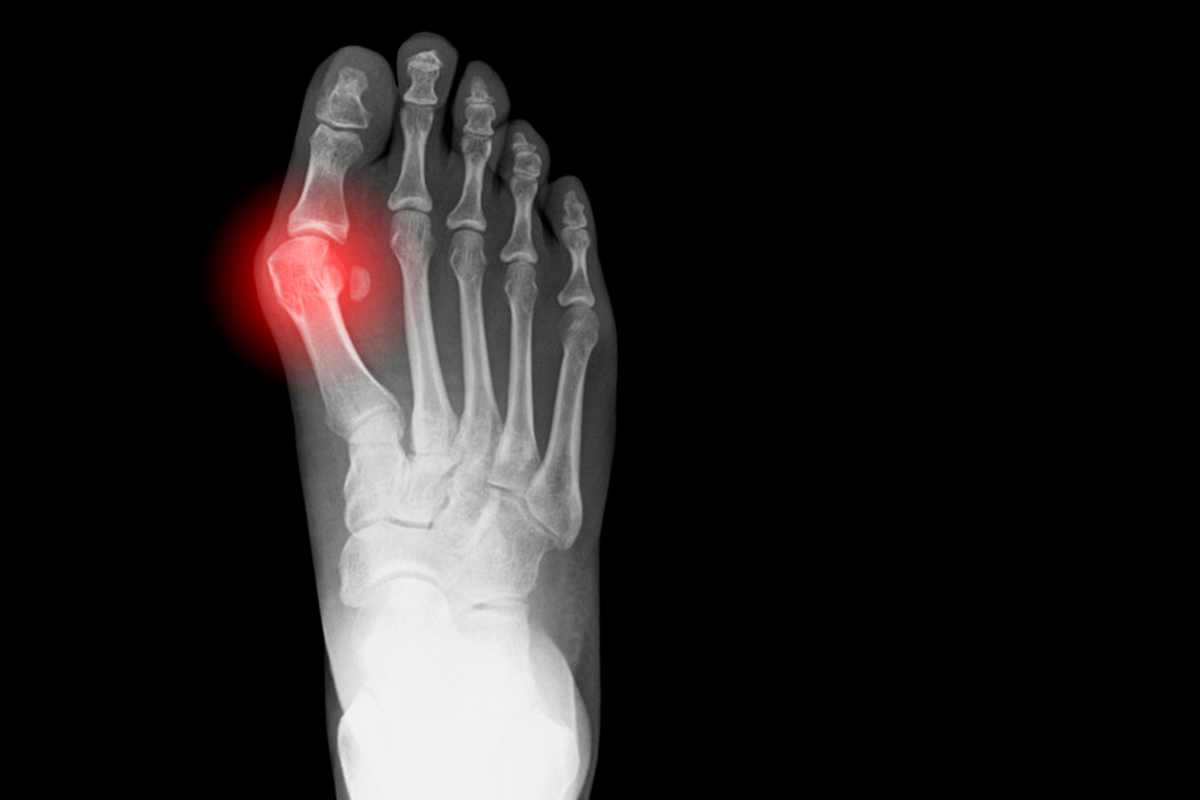

Também conhecido como hallux valgus, joanete é um problema que afeta o hallux, ou o dedão, e "empurra" ele em direção aos outros dedos do pé, consequentemente aumentando a largura do pé.

Esse problema pode causar sintomas que interferem na vida de quem o tem, como dores, inchaço, pode causar problemas nos outros dedos, inflamação e até limitar o movimento. Há diversos tratamentos para diminuir o crescimento da joanete, mas quando ele chega ao estado final o único jeito de lidar com ela é com uma cirurgia que retira uma parte do osso e rearranja o dedo.